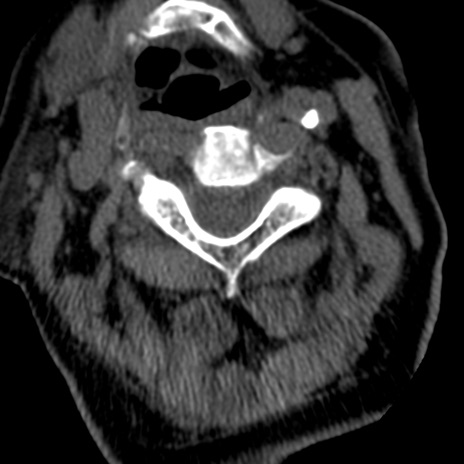

症例50 頚椎CT(横断像)

頚椎CT